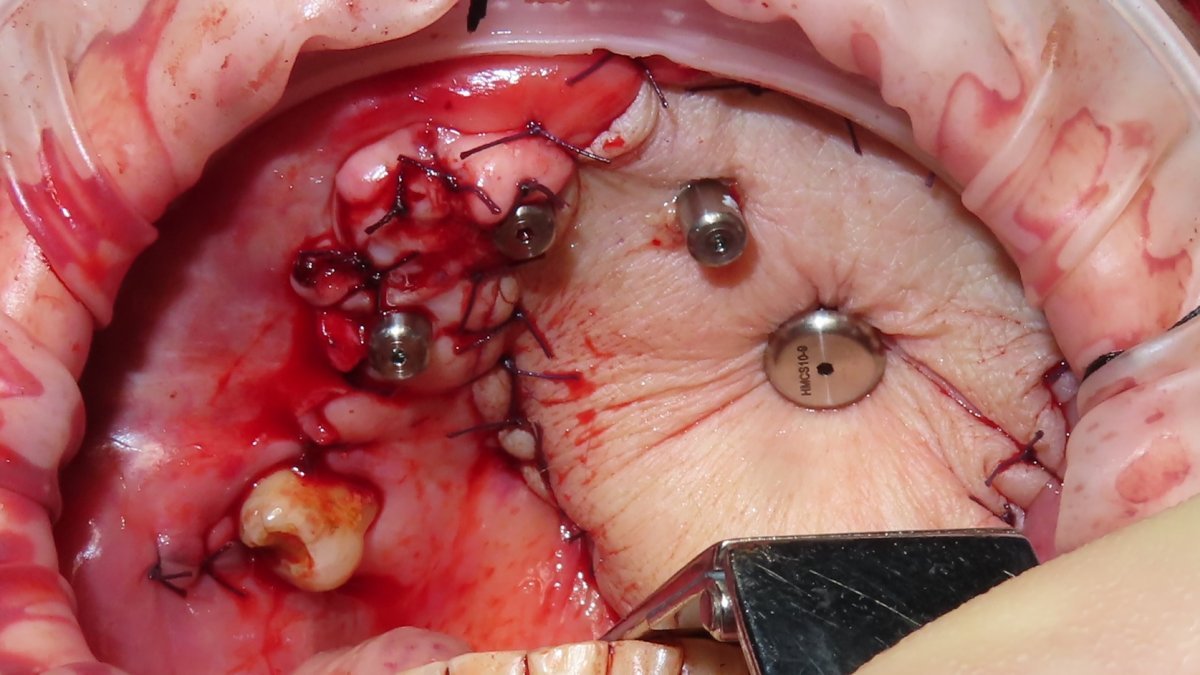

Implant Description

Quad Zygomatic Implant placement